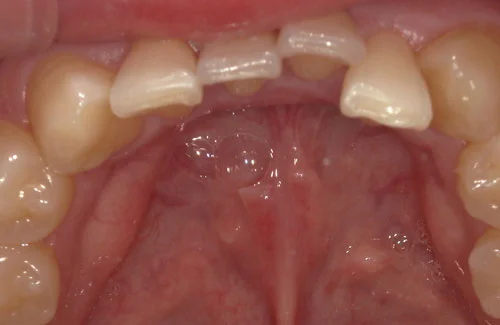

<症例7>歯がガタガタで噛み合わせが悪くお悩み

抜歯無し・マウスピースのみで矯正した症例です。

もともと歯列弓が非常に狭く、V字に近い形をしていたので噛み合わせも非常に不安定でした。

また、下顎前歯部がかなり上の方に生えていたため、下の前歯が上の前歯を突き上げてしまい出っ歯の状態になっていました。

現在では見た目はもちろん、臼歯の噛み合わせも改善しております。

患者様と症状

主訴:歯のガタガタ、噛み合わせが悪い

性別・年齢:20代女性

問題点:叢生(重度)、V字歯列弓、ディープバイト

診断:前歯部の叢生を伴うアングルⅠ級、骨格性Ⅰ級の不正咬合

主なリスク:臼歯の移動に伴い一時的に咬合しにくくなる、歯肉退縮

症状:叢生(そうせい) 過蓋咬合(かがいこうごう)

治療内容

治療期間:1年10ヶ月

治療費用:990,000円(税込)

プラン:Full2プラン

抜歯:無し

再診治療費:無し

追加治療費:無し

保定装置費:無し

治療前後の写真